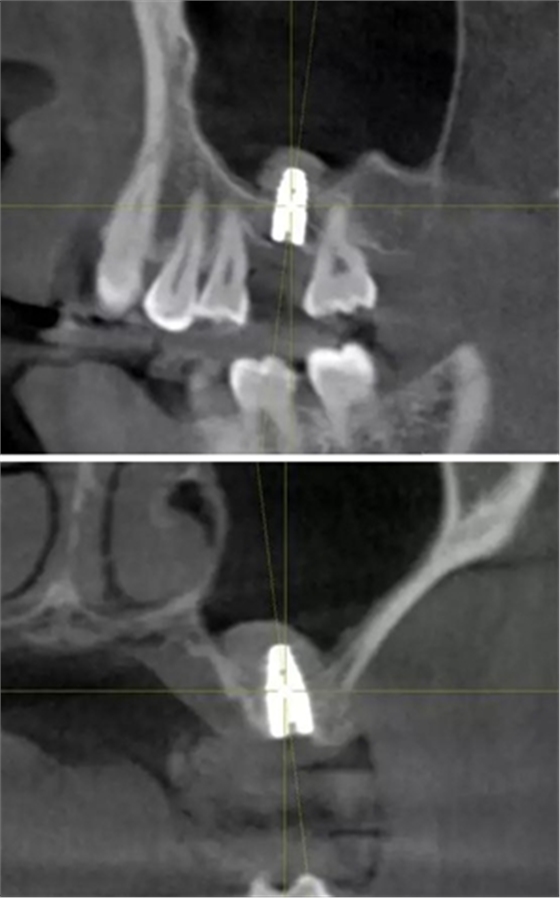

術(shù)后CBCT

提升時(shí)相關(guān)步驟可參考下面圖片

可見在完善的檢查和適當(dāng)?shù)墓ぞ哌x擇下可順利完成較復(fù)雜的上頜竇手術(shù)。